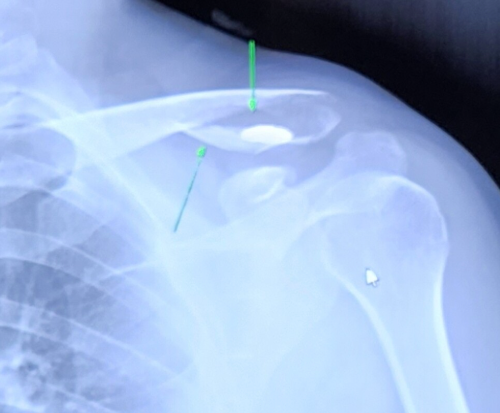

- 쇄골 골절은 견갑골과 흉골(가슴뼈)을 연결하는 뼈 중 하나인 쇄골이 부러지는 것을 말한다. 쇄골 골절은 특히 어린이와 청소년에게 흔한 유형의 뼈 손상이다.

- 쇄골 골절의 증상으로는 부상 부위의 통증과 붓기, 만짐에 대한 부드러움, 영향을 받은 팔의 움직임의 어려움, 골절 부위의 혹이나 변형이 포함될 수 있다. 심한 경우 골절된 뼈의 끝이 피부를 통해 보일 수 있다.